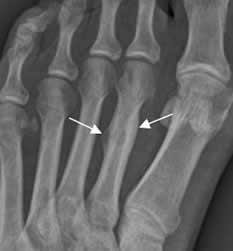

Fig 46. Fractura no desplazada.

Rx AP. Fracturas no desplazadas en las bases del 3º y 4º metacarpianos, cuyos fragmentos permanecen en contacto.